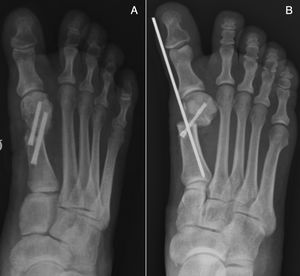

Técnica quirúrgica osteotomía de Bosch modificadaBajo las mismas condiciones antes descritas, en la osteotomía de Bosch a través de un abordaje medial, se realiza un corte recto paralelo a la carilla articular distal del metatarsiano a nivel del cuello. Se progresa de igual forma que en la osteotomía en chevron la aguja en la medular del metatarsiano para el desplazamiento cefálico lateral.

Se fija con un tornillo de proximal hacia la cabeza y de medial a lateral, y se mantiene la aguja de Kirschner (fig. 2). Se realiza la liberación percutánea del tendón aductor del hallux.

Se permite también deambulación con zapato postoperatorio con carga inmediata. Se indican curas semanales y se retira la aguja de Kirschner en consultorio en la tercera semana postoperatoria (figs. 3 y 4).